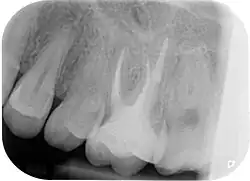

Zur Beurteilung des Erfolges einer Wurzelkanalbehandlung werden klinische Beschwerden, wie Schmerzen, Schwellungen oder Fistelgänge sowie der röntgenologische Befund herangezogen. Oft sind trotz endodontischer Infektion keine klinischen Beschwerden vorhanden, weshalb gerade die röntgenologische Kontrolle Hauptkriterium für die Beurteilung ist.[10] Neben der vorhandenen Wurzelfüllung und Veränderungen in der Wurzelphysiognomie (Resorptionen) wird vor allem der Zustand des periapikalen Gewebes begutachtet und auf das Vorhandensein einer Parodontitis apikalis oder einer radikulären Zyste geprüft.

- Wurzelkanalbehandelte Zähne mit röntgenologisch oder klinisch insuffizienter Wurzelkanalfüllung (z. B. mangelhafte Homogenität der Füllung, nicht behandelte Wurzelkanäle, nicht gefüllte Areale des endodontischen Systems, fragwürdiges und nicht mehr indiziertes Füllmaterial etc.) ohne klinische oder röntgenologische Anzeichen einer Parodontitis apicalis.

Wenn eine Verbesserung des Ausgangszustandes und eine Beseitigung der möglichen Ursachen nicht zu erwarten sind oder die Erhaltung des Zahns fragwürdig ist, ist von einer Revision abzusehen. Ebenso müssen nicht-endodontische Ursachen der Erkrankung vor einem Eingriff ausgeschlossen werden.[1] Nach Strindberg et al. wird der endodontische Misserfolg nach einer ausreichenden Heilungszeit von vier Jahren mit dem Vorhandensein einer residuellen, persistierenden oder progredienten röntgenologischen Aufhellung (Dunkler Punkt an der Wurzelspitze im Röntgenbild) und/oder mit dem Vorhandensein klinischer Beschwerden jeglicher Form definiert.[18]